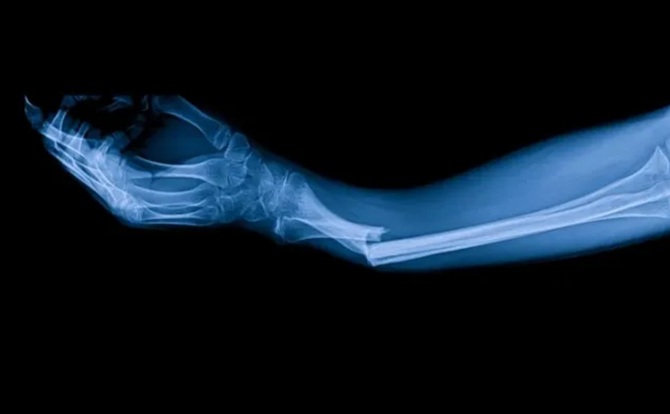

Chinese scientists were inspired by the ability of oysters to adhere firmly to wet and moving surfaces thanks to their natural bioadhesive. Using this principle, they were able to create Bone-02. In one experiment, a patient with a wrist fracture received an injection through a small incision just 3 cm long. Within three minutes, the bone had healed, whereas standard surgery would have required the insertion of a metal structure and subsequent reoperation to remove it. Three months after the procedure, the bone had healed completely and without complications. This is just one of the many successful applications of Bone-02.